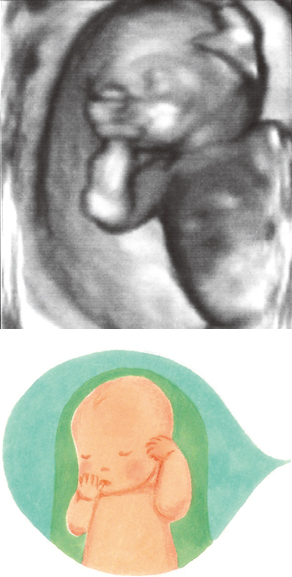

妊娠16週ころの超音波写真

羊水の中で、口を開けたり閉じたり…

赤ちゃんは、羊水の中で口を開けたり閉じたりしています。手を口元にもってくるなどのしぐさをしていることも。羊水の中でさまざまな動きをしています。